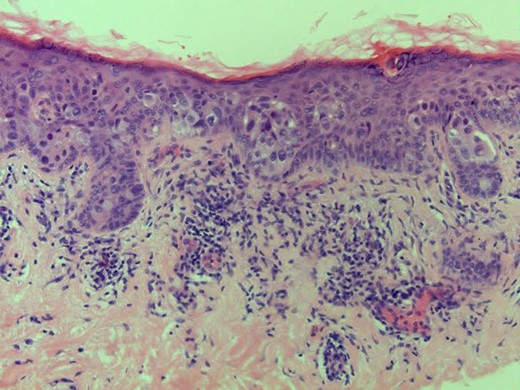

Histology: consistent with non-invasive Paget's disease of the nipplè (Fig. 1), associated with 11 mm focus of underlying high-grade DCIS of solid and micropapillary type (Fig. 2). There was no invasive disease. Sentinel node biopsy was clear.

Investigation: bilateral mammogram and ultrasound of right breast were essentially normal. Punch biopsy of right nipple showed Paget's disease with epidermal infiltration by malignant cells that were positive for Cytokeratin 7, oestrogen and progesterone receptors.